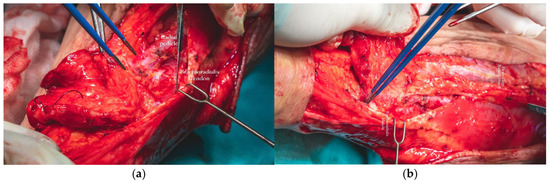

A selective neck dissection was undertaken, comprising en bloc excision of the left submandibular, submental, upper jugular, upper spinal accessory, and middle jugular lymph node levels (Figure 6). Concurrently, the left submandibular gland was excised, with careful preservation of the spinal accessory nerve to minimize postoperative functional morbidity.

Figure 6.

En bloc excision of the tumor, left submandibular salivary gland and lymph nodes.

Tumor resection was subsequently performed with a macroscopic oncologic safety margin of approximately 1 cm. The primary surgical specimen, including the neoplasm, associated lymph node groups, and the submandibular salivary gland, was removed en bloc via a transoral approach. The specimen was immediately fixed in 10% buffered formalin and submitted for definitive histopathological evaluation (Figure 7).

In parallel, dissection and identification of the left facial artery and the anterior jugular vein were performed, as these vessels were selected as the recipient sites for the subsequent microvascular anastomoses during the reconstructive phase. The chosen tissue needed to closely approximate the characteristics of the native tissues in order to ensure optimal functional and aesthetic outcomes (Figure 8a,b).

Figure 8.

(a,b). Intraoperative imagine-tongue (a). Intraoperative imagine-neck dissection-dissection–the tiro-linguo-facial trunk and hypoglossus nerve showed by blue arrows (b).